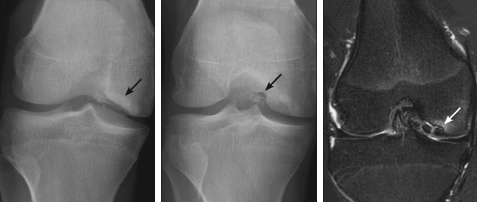

Anteroposterior, lateral, and tunnel views of the right knee are shown.

The radiographs show an osteochondral defect in the lateral aspect of the medial femoral condyle with intraarticular loose bodies. MRI of the knee, to delineate the extent of the lesion, shows an unstable, stage 4 osteochondral defect that involves the distal medial femoral condyle with at least 3 intraarticular loose bodies. In addition, there is small knee joint effusion with changes of mild synovitis.